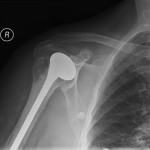

Total Shoulder Replacement